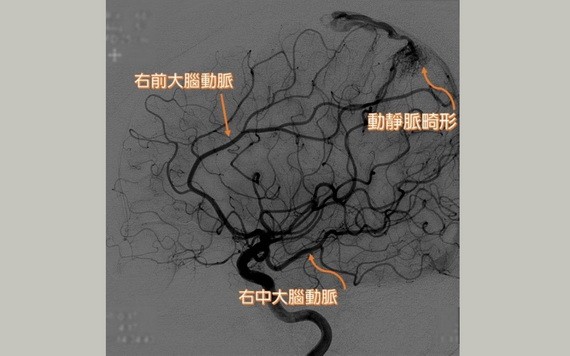

若出現異常頭痛、癲癇、半身無力時,千萬別輕忽!一名61歲喬女士無任何心血管或慢性病,日前偶有頭痛、疲憊等症狀,以為是壓力所致,某日午睡後,左半邊肢體突然無力,被同事送至急診,發現頭部右側表淺位置有出血情形,醫生評估屬非典型出血性中風,確診為先天性顱內動靜脈畸形,執行手術後,恢復狀況良好。

動脈畸形患者因腦內微血管發育不全,腦部動、靜脈交會處有不正常的畸形組織,使動脈直接注入靜脈。

台灣慈濟醫院神經外科主任徐賢達說明,腦動靜脈畸形是一種先天性疾病,正常的腦動脈會先連接到微血管,再接到靜脈,但動脈畸形患者的腦內微血管發育不全,腦部動、靜脈交會處有不正常的畸形組織,使動脈直接注入靜脈,中間無微血管做橋樑,無法供應附近的腦組織氣體與養份,導致患者出現頭痛、頭暈、噁心,甚至癲癇等症狀。

腦動靜脈畸形病灶常見於中大腦動脈區域,較常發生在20至30歲年輕族群,男女比約1:1,好發率約佔全部人口的0.1%,也佔總中風人口的1%至2%。腦動靜脈畸形依病灶大小、病灶是否在運動神經區或感覺神經區等重要功能區,及動靜脈畸形流出的靜脈位置等條件,可以將手術危險程度分成5級。

如喬女士情形,其病灶為3公分且位在腦組織接近表面處,手術風險相對低。若病灶大於3公分,且位於重要功能區,有較高的風險傷及神經造成癱瘓、語言困難或危及生命徵象等,因此手術困難度相對提高。